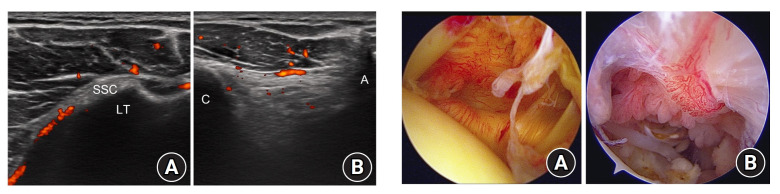

Methods: A total of 54 patients undergoing arthroscopic rotator cuff repair were selected. Doppler ultrasound was used to measure peak systolic velocity in the anterior humeral circumflex artery and Doppler activity in the glenohumeral joint and subacromial space, and these values were compared with the intraoperative synovitis score in univariate and multivariate analyses.

Results: Univariate analyses revealed that tear size, peak systolic velocity in the anterior humeral circumflex artery, and Doppler activity in the glenohumeral joint were associated with synovitis in the glenohumeral joint (P=0.02, P<0.001, P=0.02, respectively). In the subacromial space, tear size, peak systolic velocity in the anterior humeral circumflex artery, and Doppler activity in the subacromial space were associated with synovitis severity (P=0.02, P<0.001, P=0.02, respectively). Multivariate analyses indicated that tear size and peak systolic velocity in the anterior humeral circumflex artery were independently associated with synovitis scores in both the glenohumeral joint and the subacromial space (all P<0.05).

Conclusions: These findings demonstrate that tear size and peak systolic velocity in the anterior humeral circumflex artery, which can both be measured noninvasively, are useful indicators of synovitis severity. Level of evidence: IV.